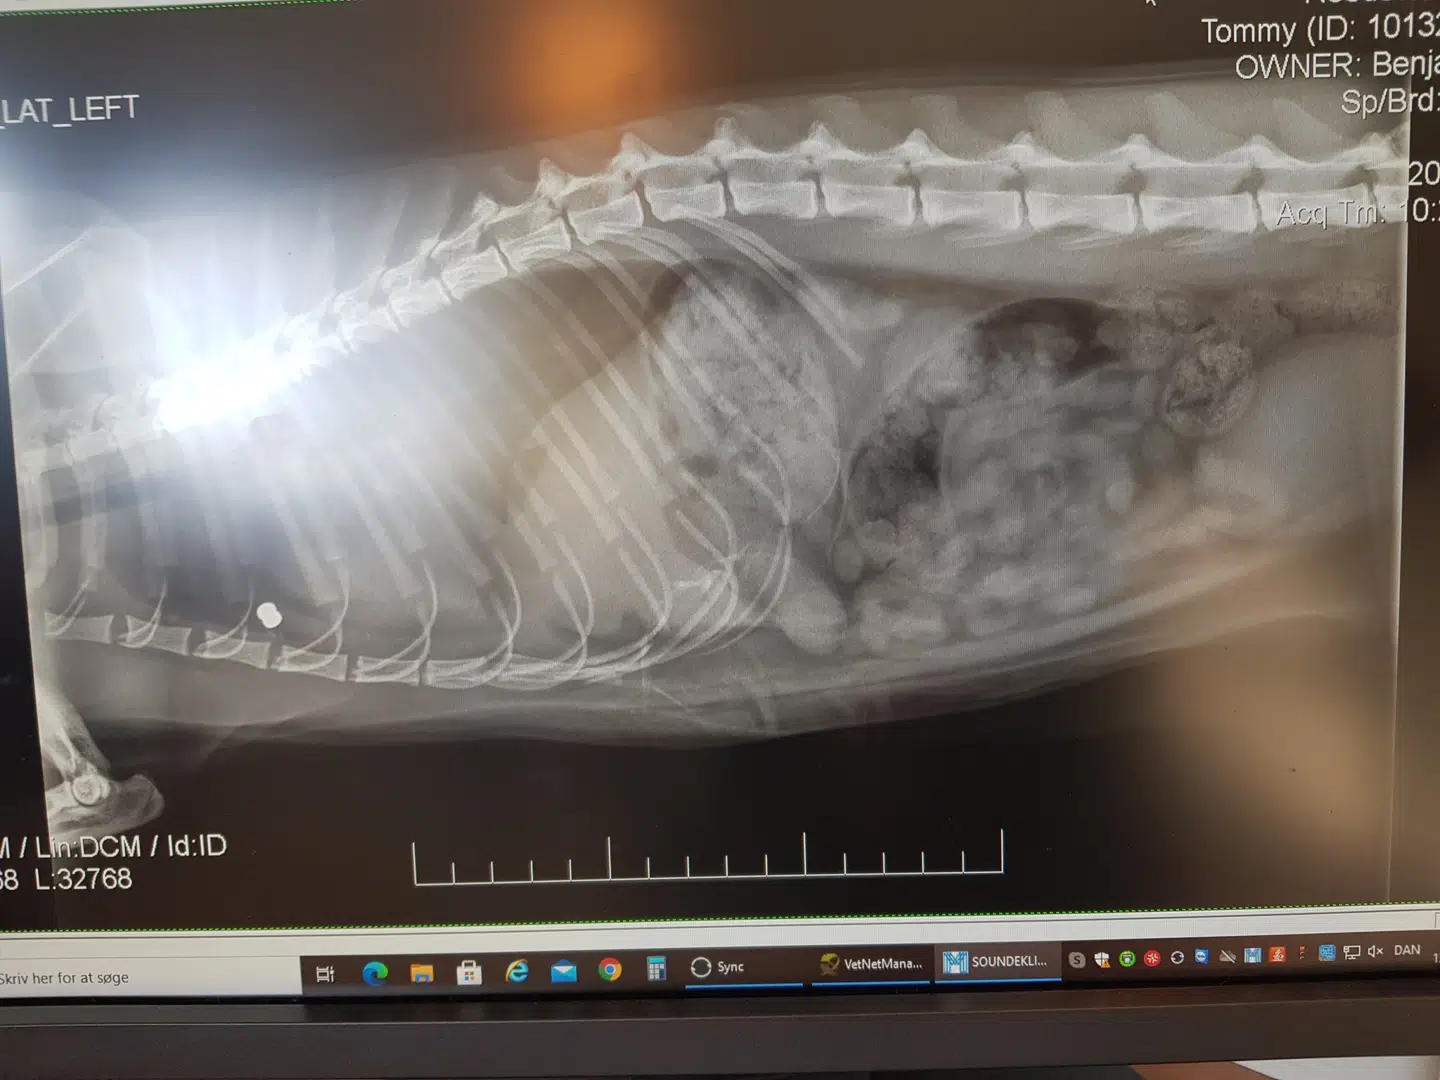

Haglet var skudt næsten hele vejen igennem hankatten og det havde resulteret i en punkteret lunge og indre blødninger.

»Vi har haft fire sager siden april og tre af sagerne på kun 14 dage,« siger Lone Paredes, der ejer Rødovre Dyreklinik, hvor hun også arbejder som fagdyrlæge.